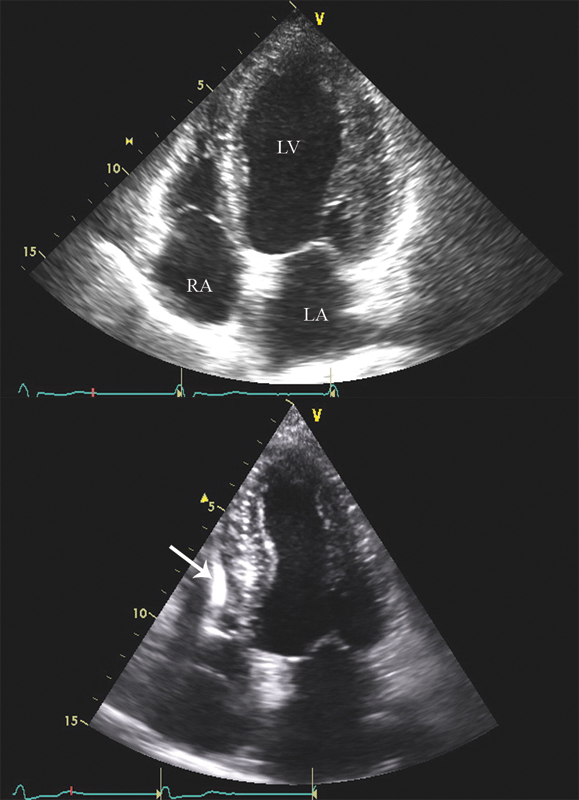

فحوصات تشخيصية لبعض امراض القلب والشرايين التاجية